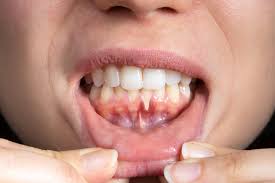

2. Bleeding During Brushing or Flossing:

• Explanation: Bleeding gums indicate inflammation. Healthy gums should not bleed during regular oral hygiene practices.